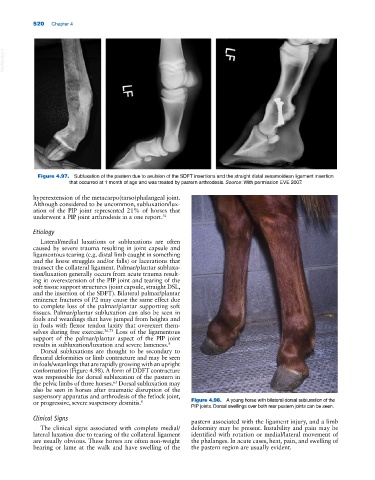

Figure 4.97. Subluxation of the pastern due to avulsion of the SDFT insertions and the straight distal sesamoidean ligament insertion

that occurred at 1 month of age and was treated by pastern arthrodesis. Source: With permission EVE 2007.

hyperextension of the metacarpo(tarso)phalangeal joint.

Although considered to be uncommon, subluxation/lux-

ation of the PIP joint represented 21% of horses that

underwent a PIP joint arthrodesis in a one report. 31